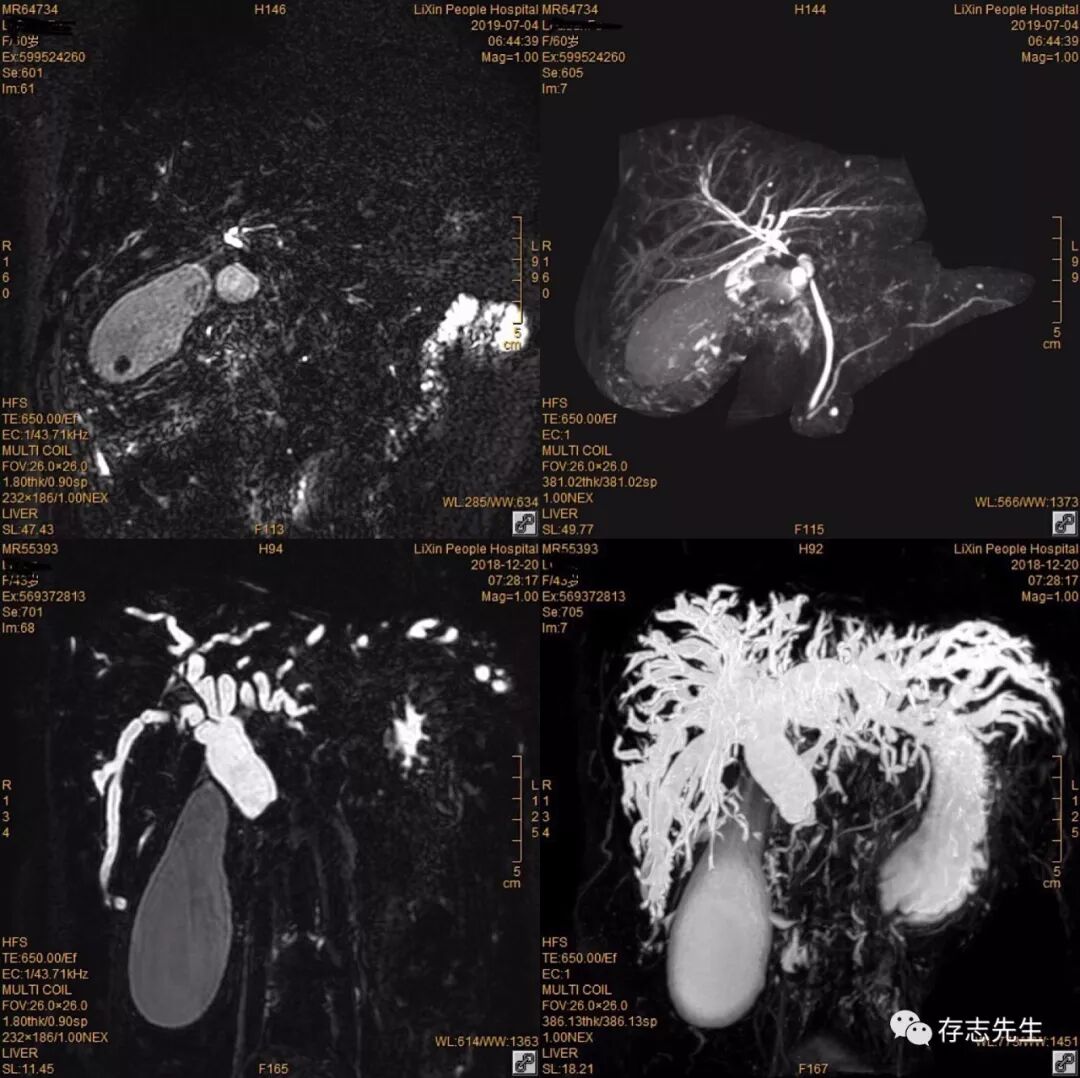

用药后胃肠道无干扰

此特性可降低缩短胃及十二指肠液的T2值从而可降低其高信号所造成的干扰背景;消除了肠道内液体T2高信号的干扰, 使MRCP胰胆管成像更加清晰, 且无任何副作用。枸橼酸铁铵溶液配制简单, 副作用小, 而且明显改善胰胆管结构的MRCP图像质量, 但服用时有少量禁忌证:高铁血症、铁剂过敏、胃穿孔、高位梗阻及孕妇与婴幼儿 。

使用方法:扫描前十分钟左右温水冲服(PS:我们一般扫MRCP都会做冠状位T2WI、轴位DWI,轴位T2WI抑脂最后做MRCP,看服药时间来调整扫描顺序!),水和药混合最好150ml左右(大概一次性杯子的量!),水不能过多,水过多不仅达不到抑制的作用,反而会适得其反!这点特别注意!